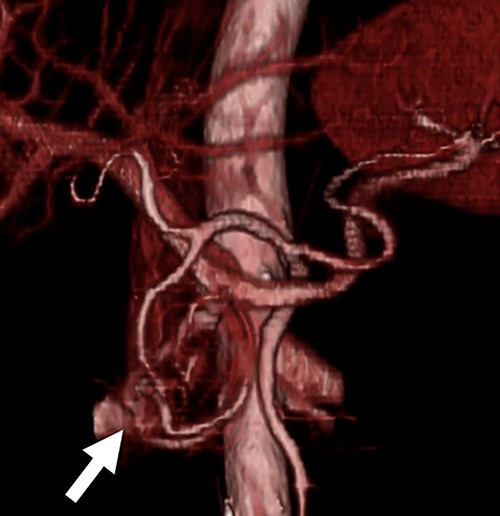

A 54-year-old man was admitted to our hospital presenting with acute upper abdominal pain. He had no family history of pancreatitis, hereditary disease or abdominal trauma; however, he had a history of habitual alcohol consumption. Blood tests showed an elevated white blood cell count (16 900/μl), serum amylase (260 U/l) and lipase (337 U/l). Contrast-enhanced computed tomography (CT) revealed meandering vessels in the pancreatic head. These vessels were enhanced in both the arterial and portal phases, while the portal vein was enhanced in the arterial phase. Swelling of the pancreatic head suggested the development of pancreatitis (Fig. 1). Three-dimensional CT revealed blood vessel communications between the arteries and veins in the pancreas (Fig. 2). Endoscopic ultrasonography (EUS) also revealed meandering vessels in the pancreatic head surrounded by low echoic lesions with diameters of 8 mm (Fig. 3). Magnetic resonance imaging (MRI) revealed flow voids and a cyst measuring 8 mm in diameter at the pancreatic head. Neither stenosis nor dilation of the main pancreatic duct was observed.

Three-dimensional CT image. The three-dimensional CT imaging showed the communication between arteries and veins in the pancreatic head (arrow).